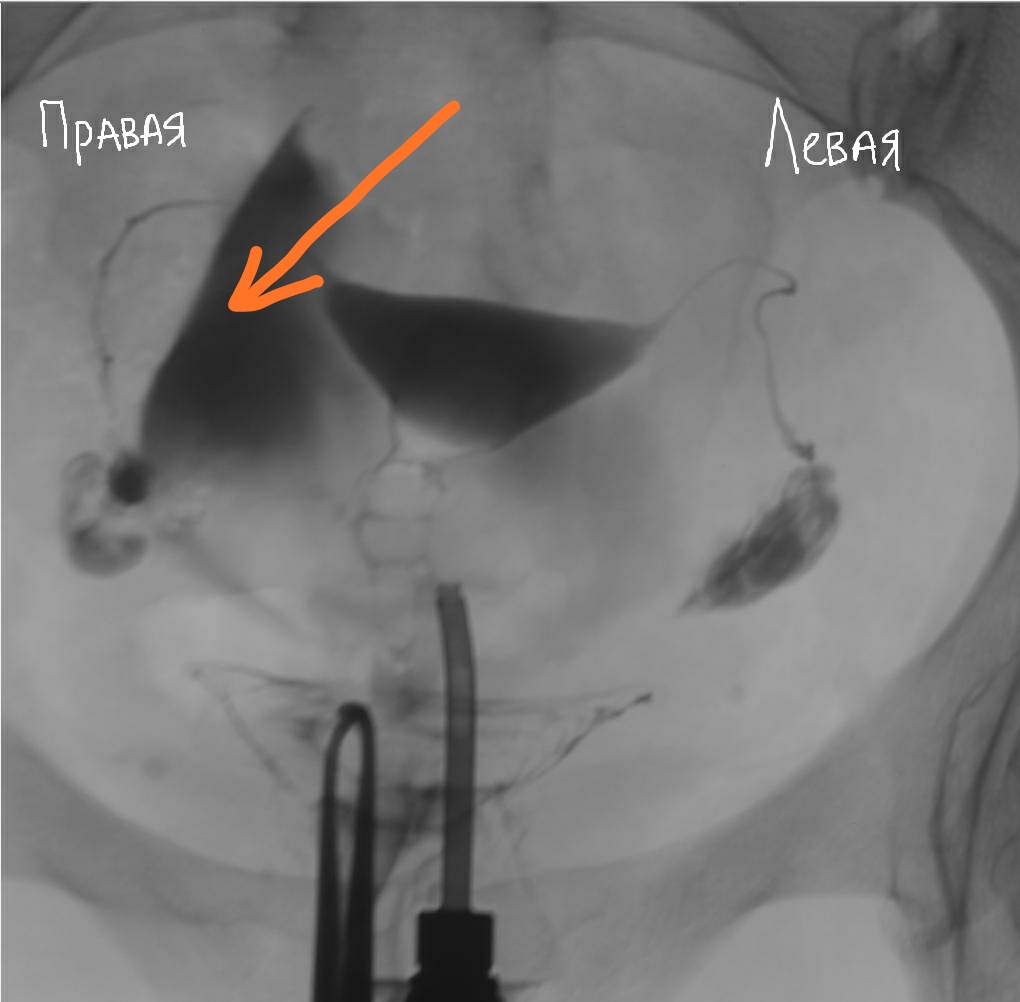

Гистеросальпингография: описание и фотографии